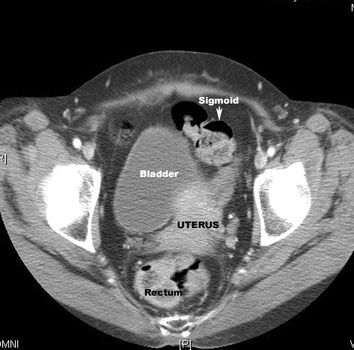

CT Pelvis |